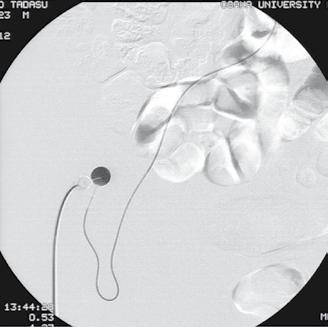

• Chemoinfuzia intraarterială reprezintă o modalitate practică prin care se introduc substanțe chimioterapice direct în tumoră, prin vasul care le alimentează; procedura chirurgicală, mimin invazivă, presupune cateterizarea supraselectivă a “feeder-ului” tumoral și cuplarea acestuia la un mic rezervor tip port-a-cath implantat în zona inghinală (abordul Seldinger fiind femural). Implantarea rezervorului subcutan este indicată desigur în situaţii în care anatomia locală o permite; cel mai facil este pentru tumora unică (primitivă hepatică) cu vascularizaţie unică, cum se observă în figura de mai jos: • Chemoembolizarea cu microparticule absorbabile (DEBDOX) oferă un nivel de consistență și repetabilitate care nu sunt disponibile chemoembolizării convenţionale și oferă posibilitatea de a pune în aplicare o abordare standardizată pentru tratamentul HCC Acest tip de procedură presupune injectarea în interiorul tumorilor a unor microsfere absorbabile în timp, acestea fiind încărcate în prealabil cu o substanță chimioterapică, Doxorubicin sau derivați (Adriamicin, Idarubicin - studiu facut de Prof. Boris Guiu, Universitatea Montpellier - Farmarubicin,etc) în cazul pacienților cu carcinom hepatocellular. Injectarea microsferelor trebuie facută superselectiv, cât mai distal posibil, așa cum este ilustrat în figura de mai jos: